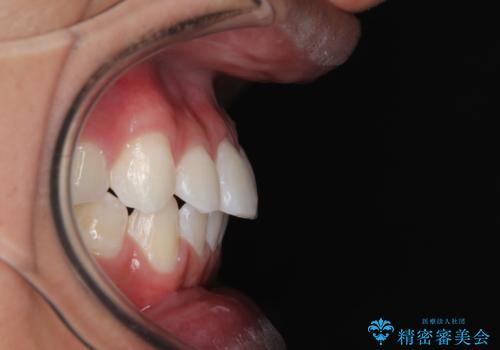

- 前歯のデコボコを気にして来院された患者様です。

ワイヤー装置でもマウスピースでも対応可能でしたが、自己管理の煩わしさを気にされ、ワイヤー装置にて矯正治療を行うこととしました。